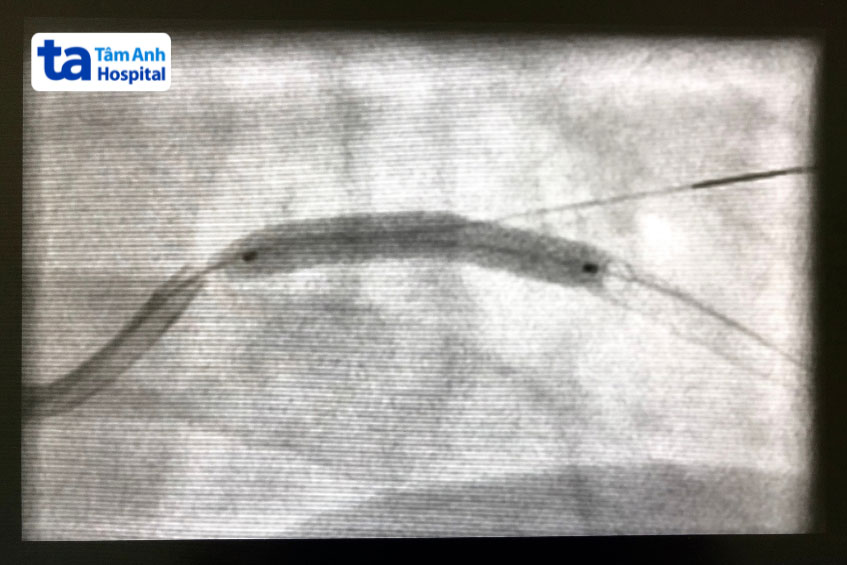

Sau khi bệnh nhân được gây tê tại chỗ, bác sĩ can thiệp sẽ tiến hành đưa một ống thông nhỏ (catheter) vào hệ mạch thông qua động mạch đùi hoặc động mạch quay. Dưới hướng dẫn của hệ thống chụp mạch số hóa xóa nền (DSA) kết hợp với thuốc cản quang, ống thông được luồn đến vị trí tổn thương trong lòng động mạch vành.

Khi đã xác định chính xác vị trí hẹp/tắc nghẽn, một bóng nong gắn ở đầu dây dẫn sẽ được đưa qua tổn thương và bơm căng. Tiếp theo, stent phủ thuốc sẽ được đưa đến đúng vị trí cần điều trị. Khi bóng được bơm căng, stent bung ra, áp sát vào thành mạch và cố định tại chỗ. Sau đó, bóng được xì hơi và rút ra, để lại stent bên trong lòng mạch. Stent sẽ từ từ giải phóng thuốc chống tăng sinh tại chỗ, giúp ngăn ngừa hiện tượng tái hẹp sau can thiệp.

Sau khi kiểm tra lại hình ảnh mạch để đảm bảo stent nằm đúng vị trí và dòng chảy đã được tái thông tốt, bác sĩ sẽ rút ống thông, tiến hành băng ép tại vị trí chọc mạch và kết thúc thủ thuật.